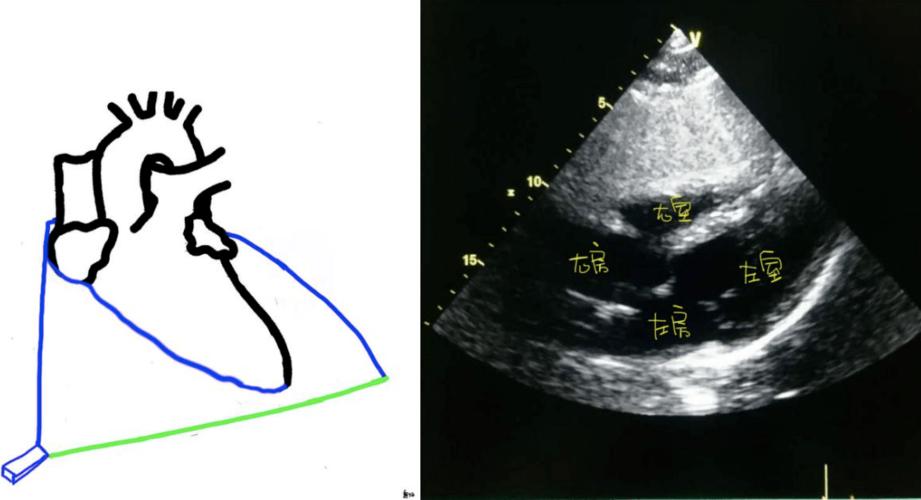

心尖四腔观变异切面

心尖五腔心切面示意图

超声心尖五腔心示意图